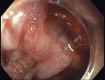

Every trick in the book: EUS angiotherapy for management of refractory bleeding secondary to a complicated duodenal ulcer in a patient with Roux-en-Y gastric bypass